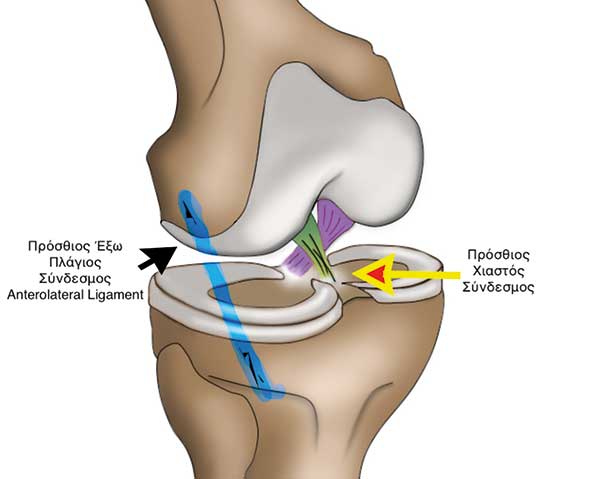

Η επιστηµονική κοινότητα κατανόησε πως η συνδεσµοπλαστική του προσθίου χιαστού δεν οδηγεί πάντοτε στα επιθυµητά αποτελέσµατα. Το 2013 ο Steven Claes από το Βέλγιο σε µια προσπάθεια κατανόησης της υπολειπόµενης στροφικής αστάθειας δηµοσιεύει την ανακάλυψη ενός νέου συνδέσµου από την έξω πλευρά του γόνατος, του προσθίου έξω πλαγίου συνδέσµου (anterolateral ligament). Οι εµβιοµηχανικές µελέτες που ακολούθησαν επιβεβαίωσαν τον σηµαντικό στροφικό σταθεροποιητικό ρόλο του πρόσθιου έξω πλάγιου συνδέσµου (anterolateral ligament) (Εικόνα 2).